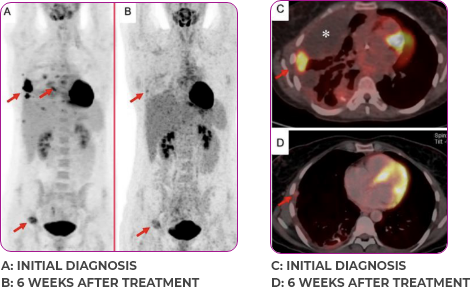

Response in primary and metastatic lesions1

Images courtesy of Dr Steven Waguespack.

Response to VITRAKVI1,2

- Confirmed partial response (92.6% reduction in target lesions)

- Treatment continued for 55 cycles

- VITRAKVI was well tolerated; patient did not have to discontinue due to AEa

- No treatment interruptions or dose reductions